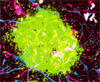

Макрофаги — эффективное оружие, используемое иммунной системой для поглощения болезнетворных микробов. Однако, как показали немецкие микробиологи, некоторые бактерии не только не гибнут в «желудках» макрофагов, но даже ухитряются использовать их в качестве... инкубаторов.